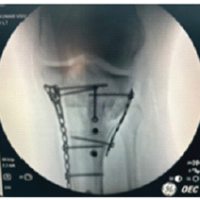

The planned surgical intervention included the reduction and fixation of the ACJ. We used a wire cerclage in a figure-eight pattern for the ACJ and performed medial clavicle fixation using a 3.5 reconstruction plate anteriorly. X-rays showed good reduction, and clinically, there was no “piano key” sign. However, we still placed an endobutton to ensure stability under arthroscopy (Fig. 4).

Figure 4: Pre-operative marking. Medial clavicle fixation using an anteriorly placed 3.5 mm reconstruction plate. Acromioclavicular joint wire cerclage in a figure-eight pattern and an endobutton placed arthroscopically.